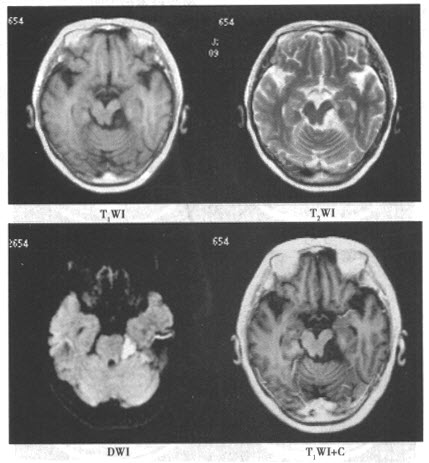

患者,女,28岁。因左侧面部疼痛1年余入院,影像学检查如下图。

该患者最有可能的诊断是()

患者,女,28岁。因左侧面部疼痛1年余入院,影像学检查如下图。该患者最有可能的诊